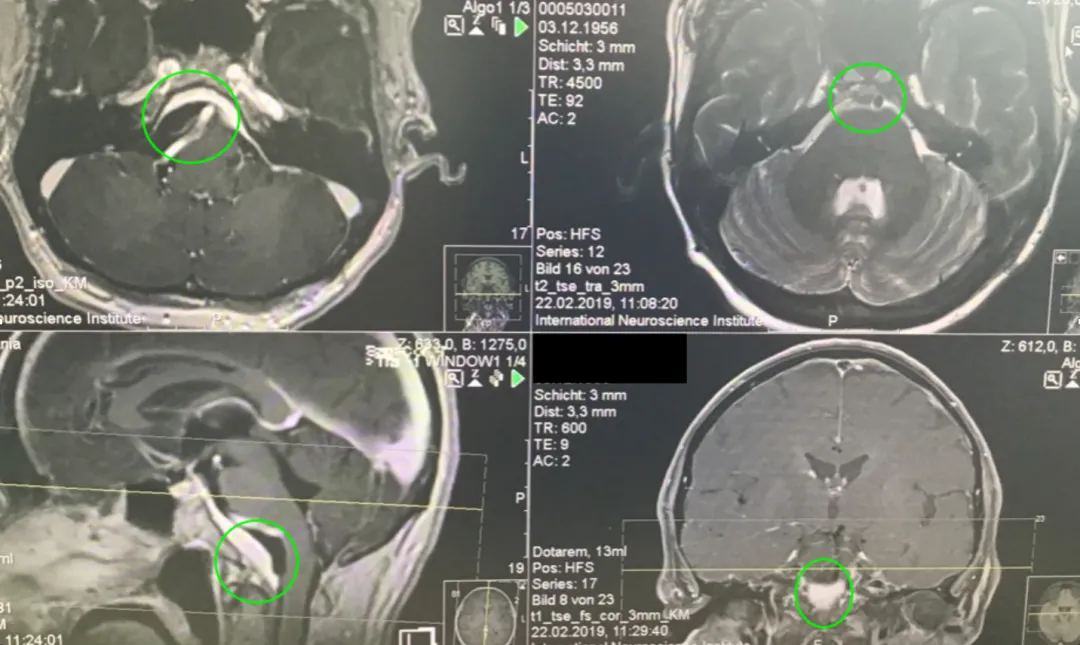

40+岁,女性,持续1年多的症状加重——相继出现头痛、复视、肢体无力、吞咽困难等,当地医院诊断为巨大岩斜区脑膜瘤,辗转多地医院均告知手术风险大,术后并发症风险发生率高,后寻求INC巴特朗菲教授手术治疗,肿瘤近全切,无相关手术并发症。

术前MR示:岩斜区巨大脑膜瘤,压迫脑干、颅神经,侵犯基底动脉等

术后MR显示:肿瘤近全切除,术后未见脑血肿、脑水肿,神经血管、脑干等组织保护完好